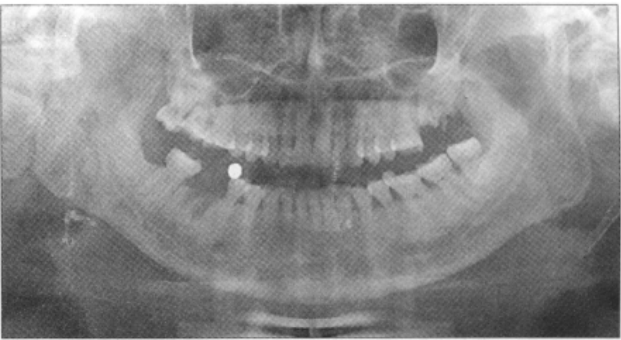

患者,男,45岁,2010年5月5日因右下颌第一磨牙拔除1个月后至颌面外科就诊,要求种植修复缺失牙。患者于1个月前,右下第一磨牙根尖周炎在外院行根管治疗,根管治疗失败后给予拔除,拔除术3d后无明显不适。

专科检查:右下第一磨牙缺失,牙龈愈合尚可,颊侧骨板斜形吸收,可用骨宽度约为7mm,右下第二前磨牙及第二磨牙稍前倾。

X线检查:右下第一磨牙拔牙窝依然清晰,未见明显的新骨生长愈合,可用骨高度约为12.5mm